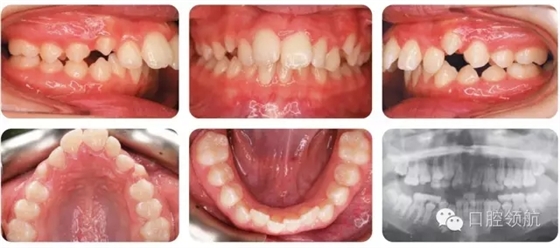

12歲的女性患者,由全科牙醫(yī)轉(zhuǎn)診。該患者健康情況良好,主訴是前牙前突(圖2.1)。

圖2.1

口內(nèi)相中的牙列處于哪一階段?

早期恒牙列。除LL7部分萌出以外,其余第二磨牙尚未萌出。

錯牙合的主要特點有哪些?

● 安氏II類1分類,深覆蓋,深覆牙合,下前牙咬在上前牙腭側(cè)黏膜。

● 右側(cè)磨牙1/2牙尖Ⅱ類關(guān)系,左側(cè)磨牙I類關(guān)系。

● 中線一致。

● UL2多生牙已萌出。